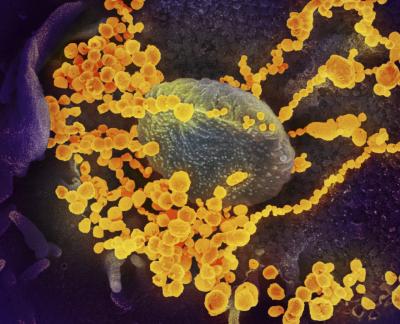

स्कॉटलँड स्कूल ऑफ लाईफ सायन्सनी कोरोना व्हायरसच्या काही प्रिंट्स फोटो दाखवले आहेत. त्यात असं दिसून येत आहे कोरोना व्हायरसचं आतड्यांवर फक्त संक्रमण होत नसून कोरोना आतड्यांमध्ये वेगाने पसरत जातो.

माणसाच्या शरीराला संक्रमित करून आतड्यांपर्यंत पोहोचत असलेला कोरोना व्हायरस पांढऱ्या रंगाचा दिसतो. कोरोनाचे निरक्षण करण्यासाठी शास्त्रज्ञांनी अल्ट्रा पॉवरफुल मायक्रोस्कोपचा वापर केला.

शरीरातील कोरोना व्हायरसची माहिती देणारे हे फोटो ३० ते ५० गीगाबाईट्सचे आहेत. स्कूल ऑफ लाईफ सायन्सचे क्वारंटाईन सेल बायोलॉजी प्रोफेसर यांनी सांगितले की, कोरोना व्हायरस आतड्यांपर्यंत पोहोचून शरीराचं नुकसान करत असतो. आतड्यांमध्ये व्हायरसची संख्या वेगाने वाढत जाते.